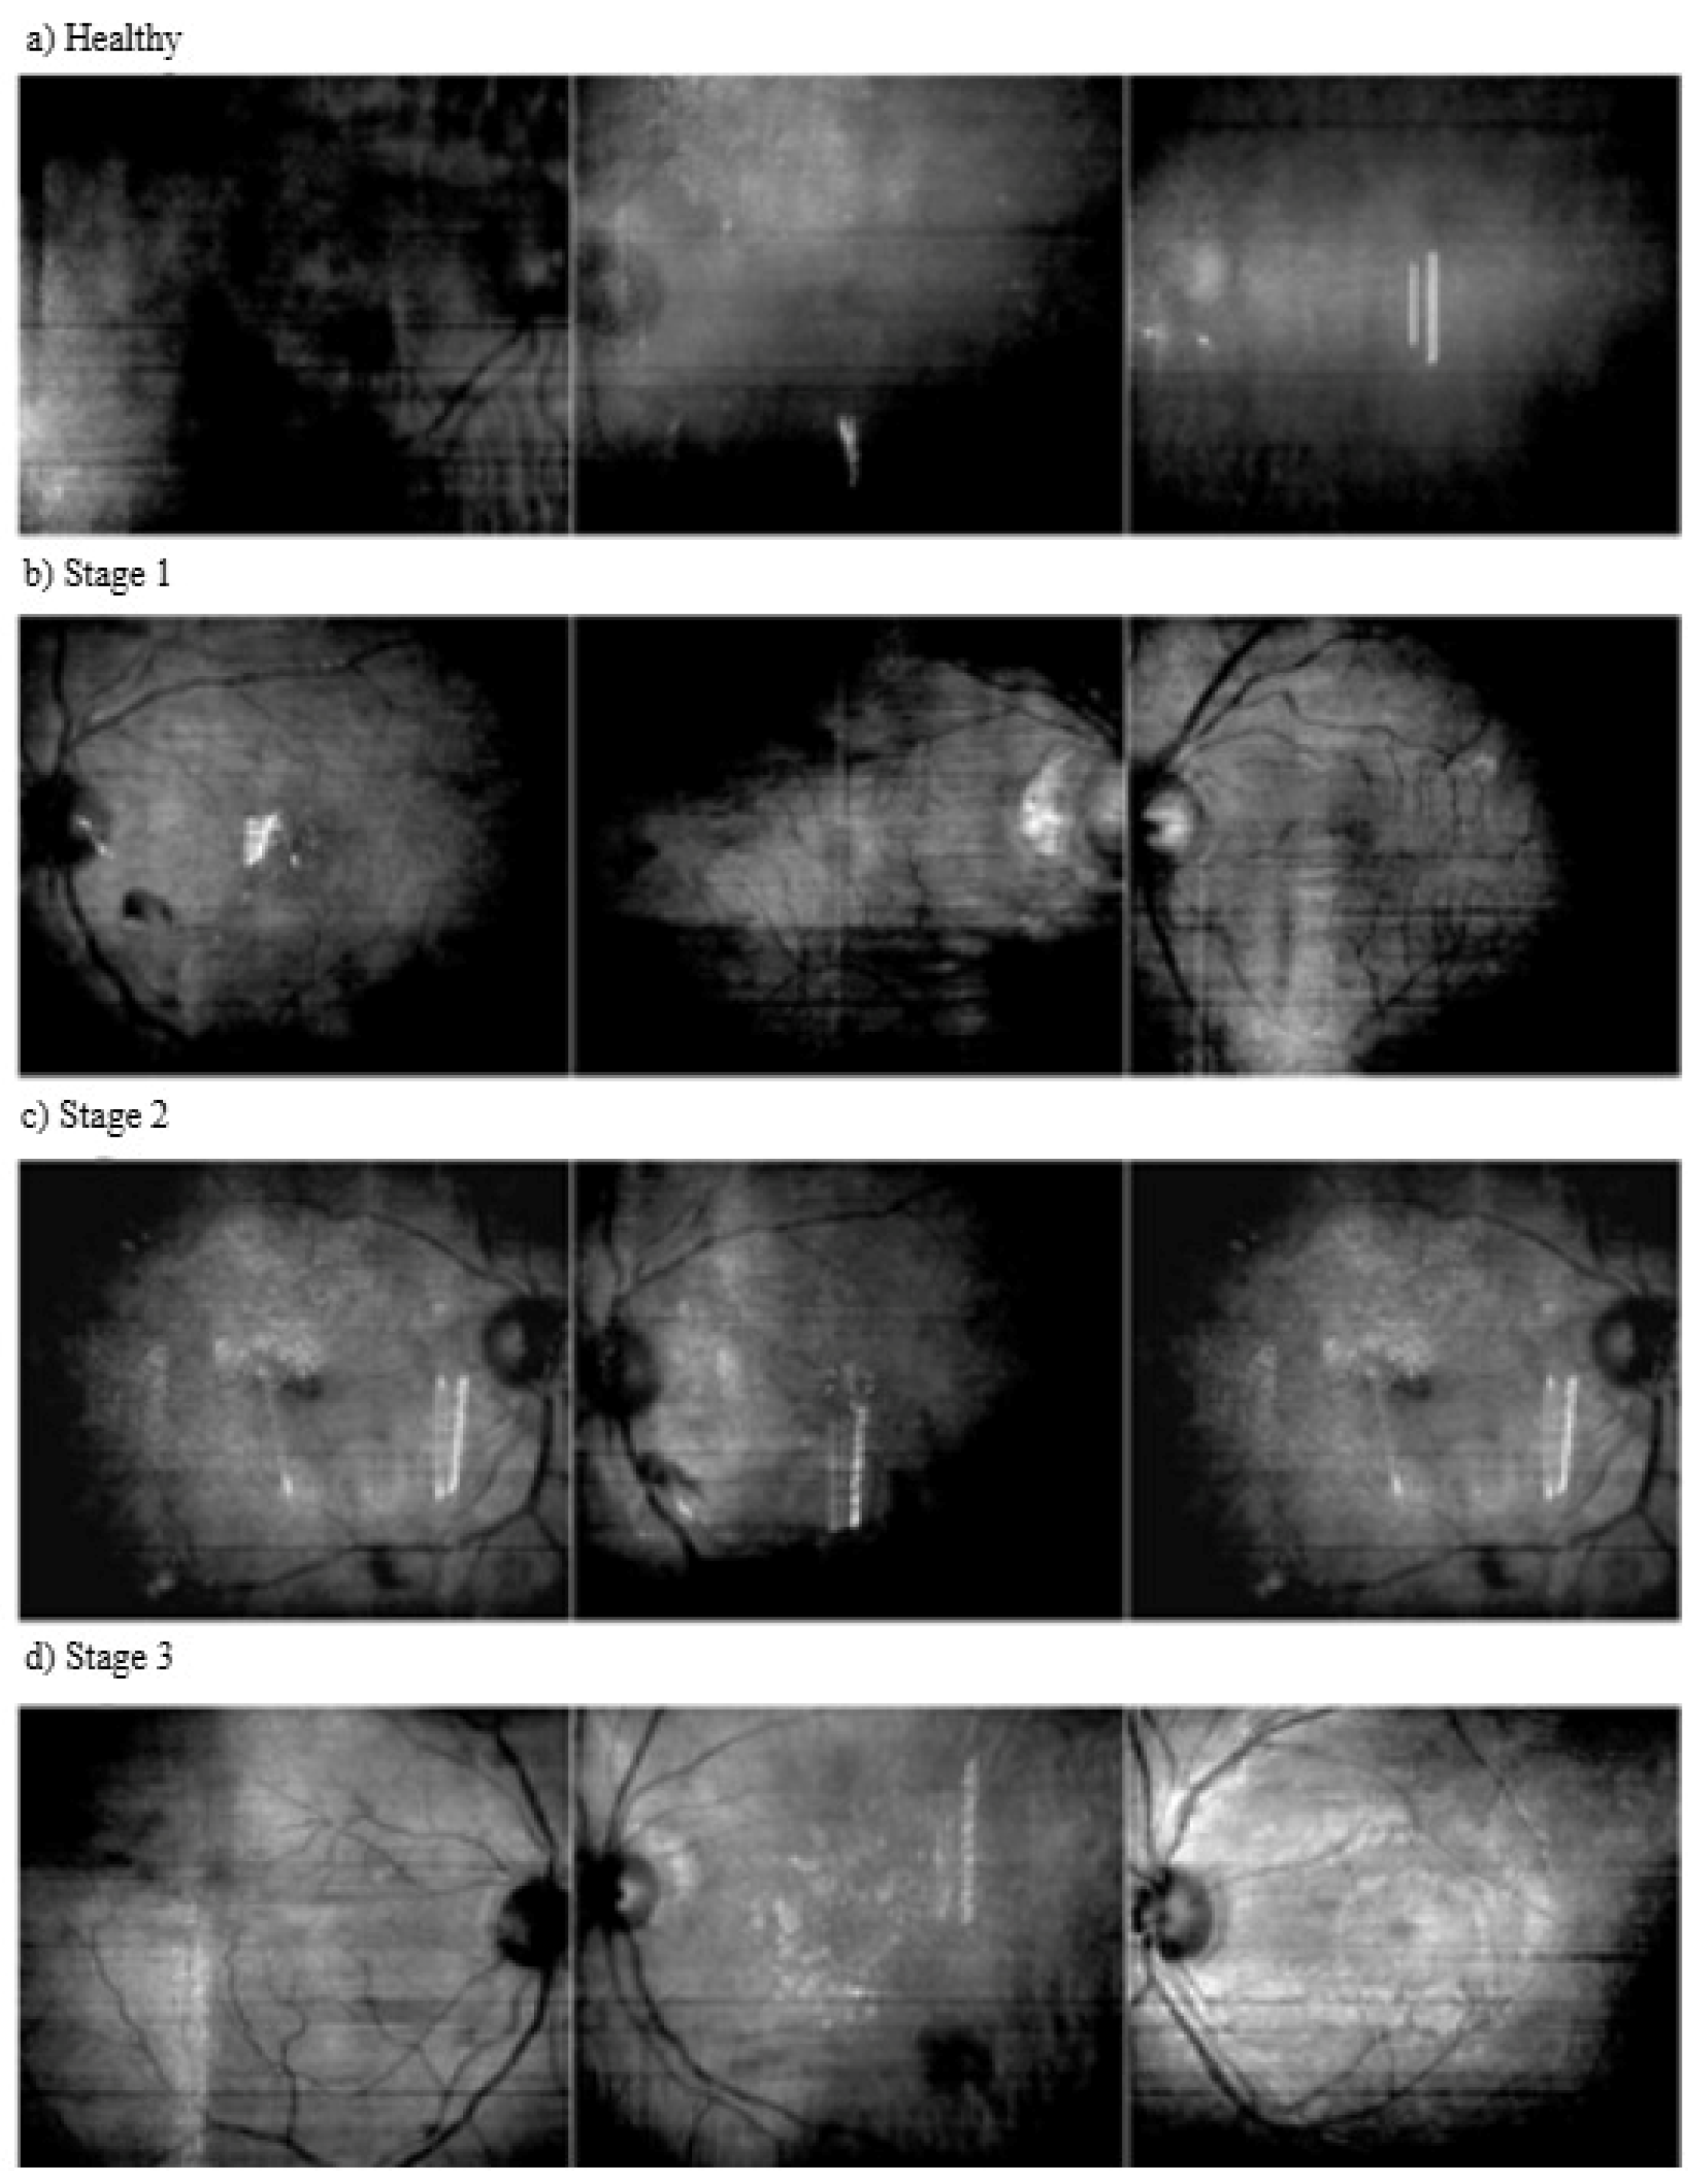

| Category | Identification |

|---|---|

| Normal | No hypertension-related changes or abnormalities in the retina. |

| Stage 1 | A condition with mild arterial narrowing and thickening of the vessel walls. |

| Stage 2 | A condition with more pronounced vasoconstriction, arteriovenous crossing and atherosclerosis. |

| Stage 3 | A condition involving serious vascular disorders with hemorrhages, exudates and cotton wool-like spots in the retina. |